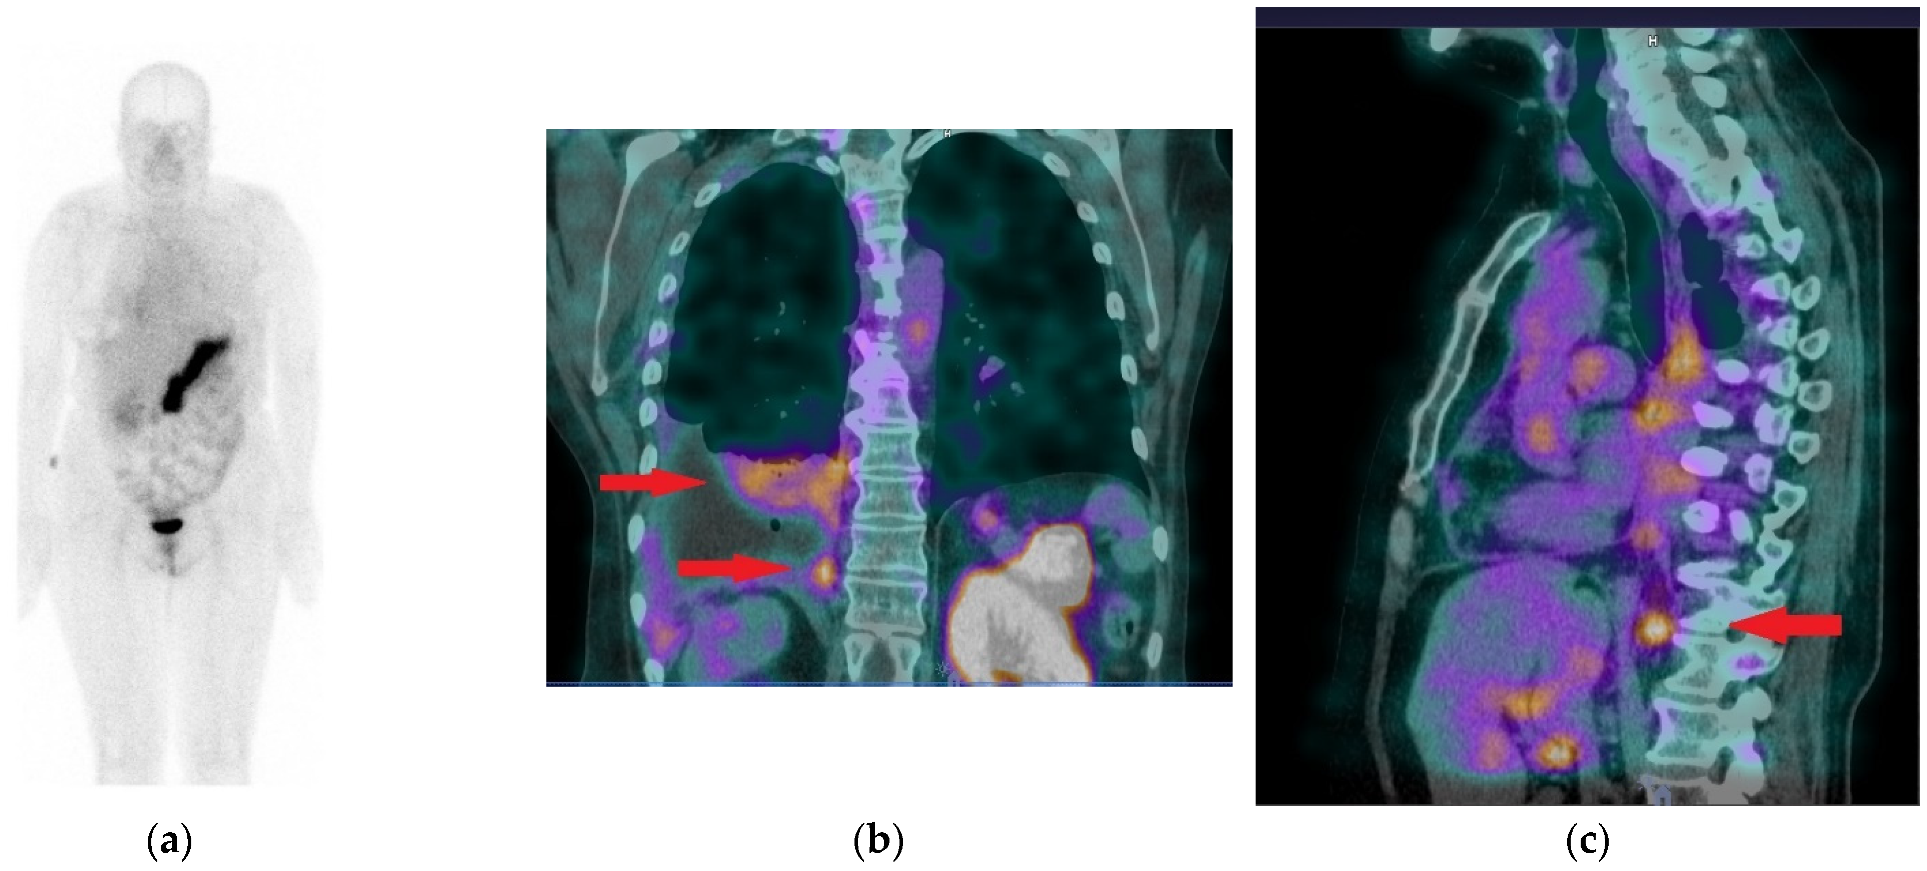

3.6. First Results of [99mTc]Tc-DB15 in BC Patients Applying SPECT/CT

3.6.3. Pathological Findings